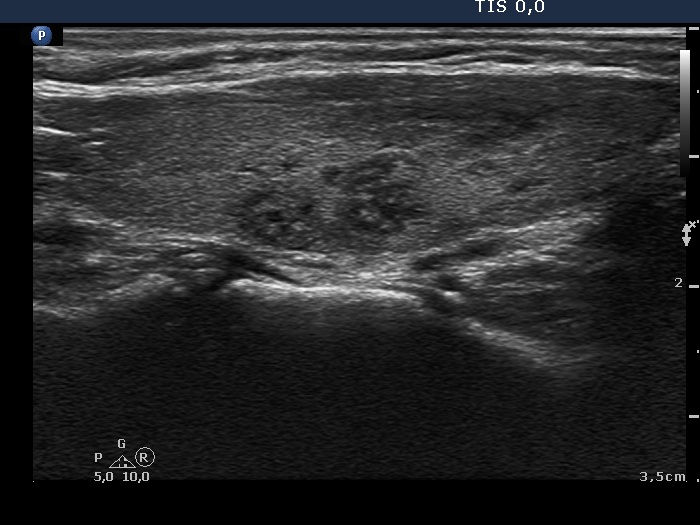

Discrete lesion or nodule in Hashimoto's thyroiditis - case 7 (1459) (ultrasonographic picture 3)

Right lobe, another longitudinal view.